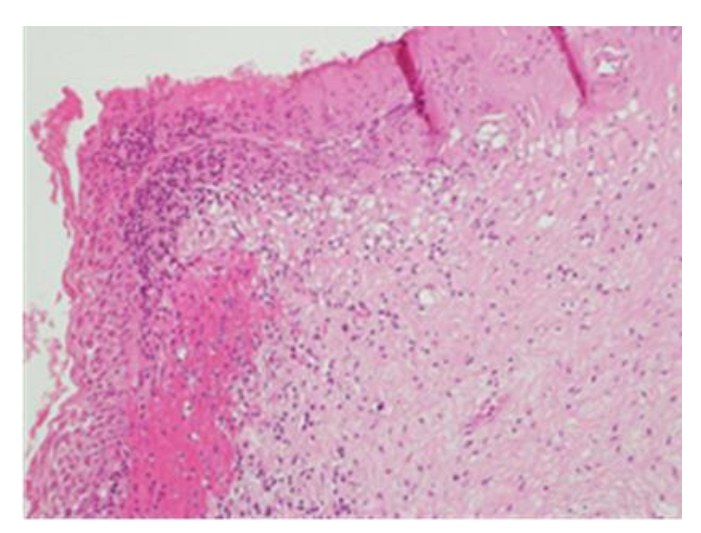

Figure 3.

Histological sample of the excised tissue representing the main portion of the excised cervix. Morphologically, enlarged and hyperchromatic nuclei, clumped chromatin, irregularities, notches in the nuclear membrane, and an altered nuclear/cytoplasmic ratio can be observed. The lesion appears extensive at the electroresorptive margins. The lesion is compatible with a diagnosis of CIN3, with an aggravation of the initial CIN2 pathology.